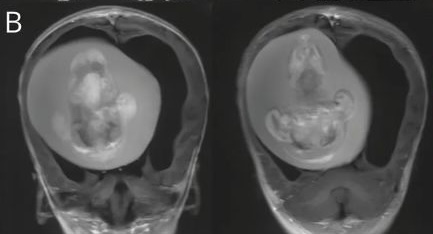

腦中有一個約10公分的胎兒

醫療團隊經檢查後發現女嬰的腦內竟然有一個約10公分的胎兒,且從照片中可見脊椎、上肢、骨骼似乎都已長出來了,不過未發育完整,因此研判是女嬰的雙胞胎姊妹。而這種胎兒留存在另一名胎兒體內的情況是一種發育異常,稱之為「胎中胎」(Fetus-in-fetu)。